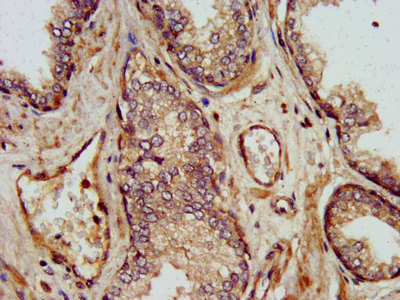

IHC image of CSB-PA867119LA01HU diluted at 1:500 and staining in paraffin-embedded human prostate cancer performed on a Leica BondTM system. After dewaxing and hydration, antigen retrieval was mediated by high pressure in a citrate buffer (pH 6.0). Section was blocked with 10% normal goat serum 30min at RT. Then primary antibody (1% BSA) was incubated at 4°C overnight. The primary is detected by a biotinylated secondary antibody and visualized using an HRP conjugated SP system.